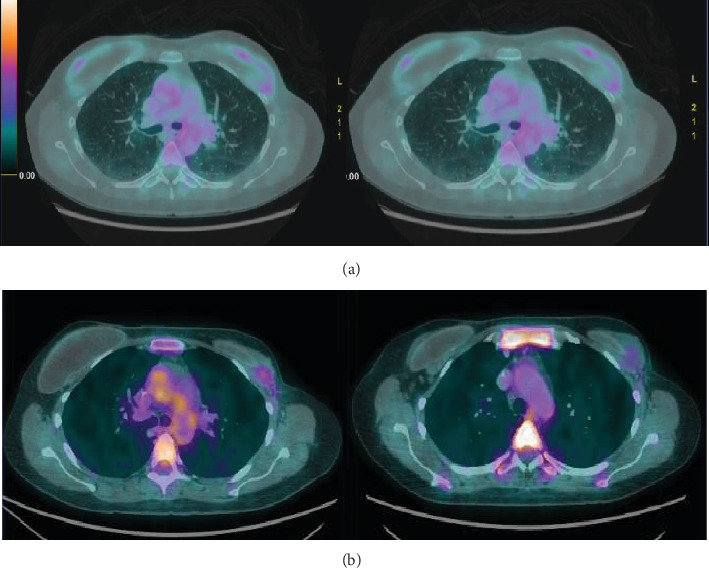

Abstract Image